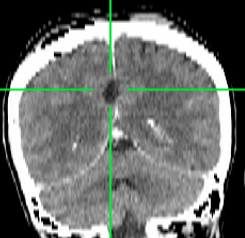

Spotāns intracerebrāls saasiņojums (hematoma)

Redzams saasiņojums smadzeņu vielā pirms operācijas

Pēcoperācijas attēls - saasiņojums no smadzenēm evakuēts